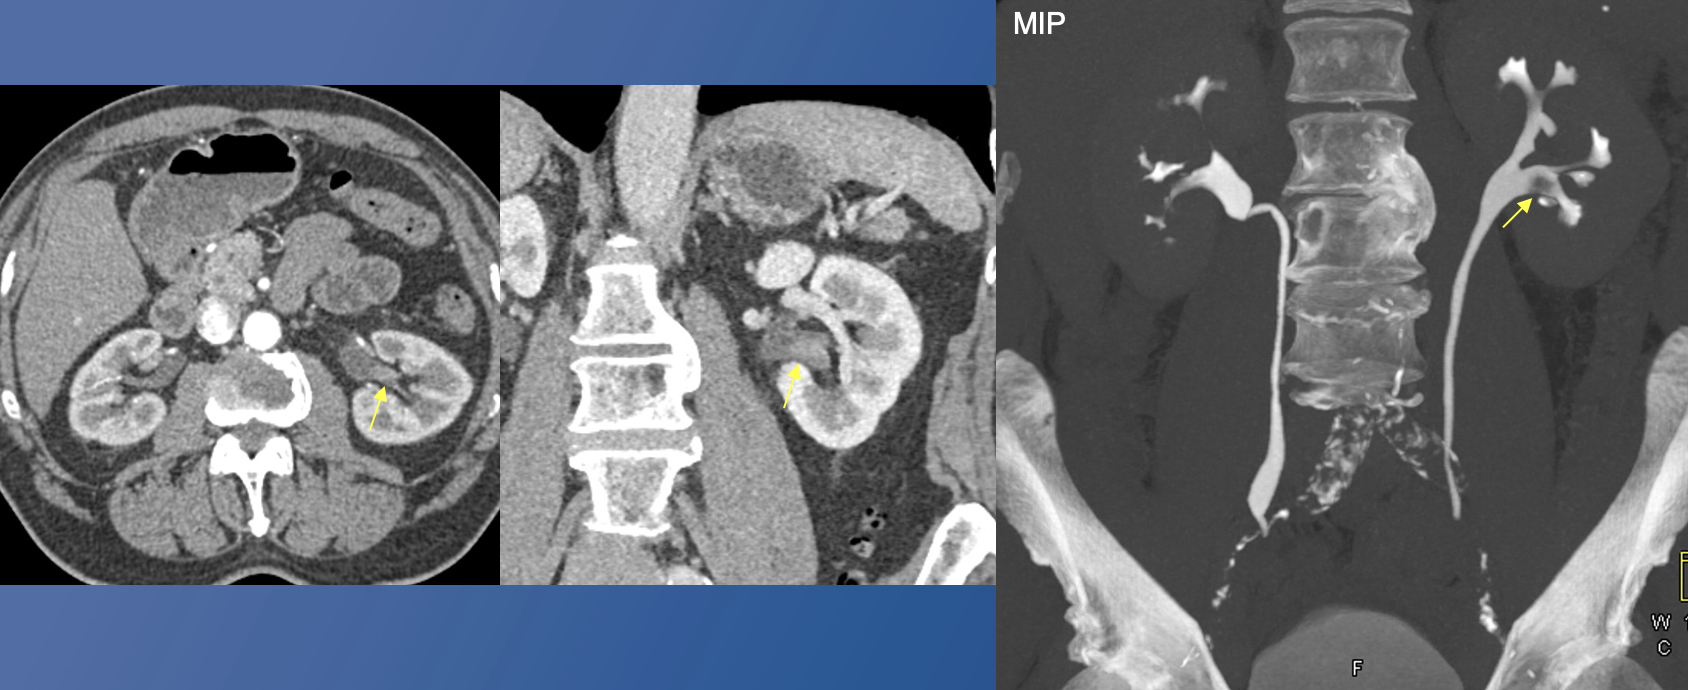

22. Ill-defined soft tissue mass in left upper pole calyces + New mass arising from left renal pelvis + metastatic lesion to left ureter High-grade UTUC on biopsy ![]() |